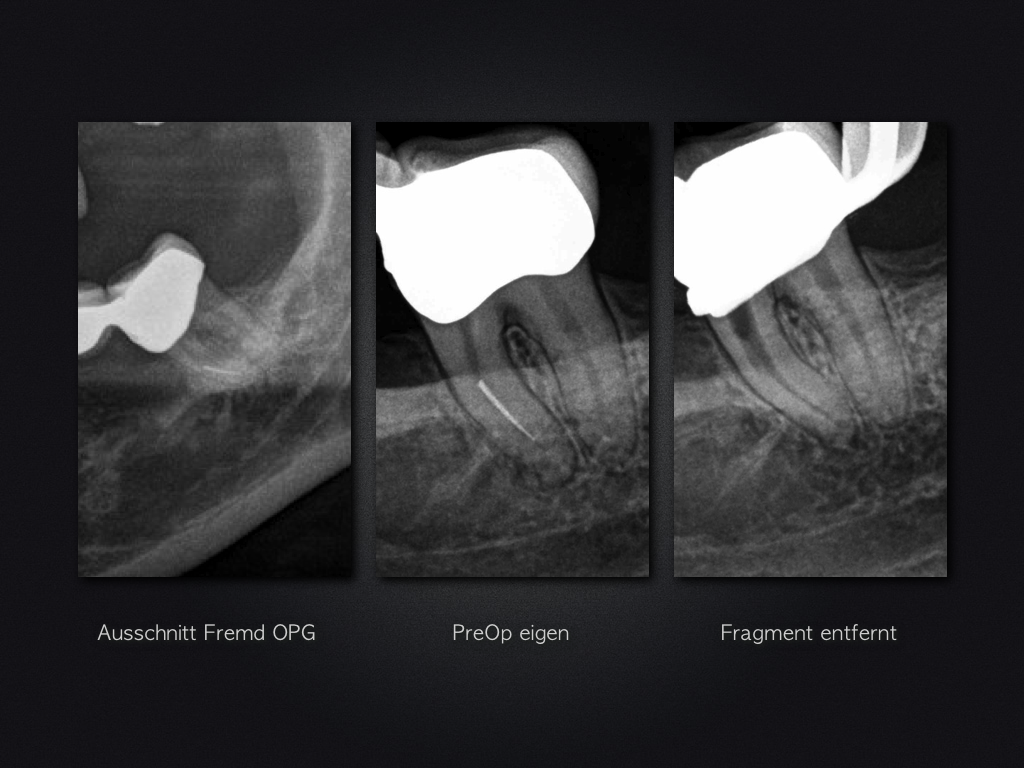

Glück gehabt